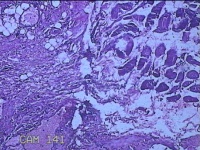

右手掌肿物

性别

女

年龄

32岁

临床诊断

1.右手掌肿物性质待查?右腕管综合征

一般病史

发现右手掌肿物疼痛伴拇示中指感觉迟钝约6年。

标本名称

大体所见

灰白粉红色肿物2.5x2x0.8cm一个,表面光滑,切开肿物呈实性,切面灰白粉红色,质软。